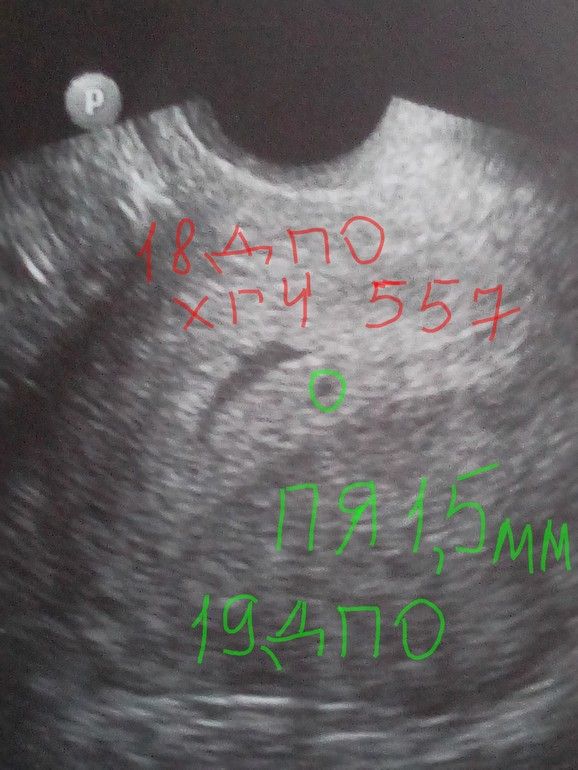

на 18 дпо 557

на 19 дпо на УЗИ увидели плодное яичко всего 1,5 мм.